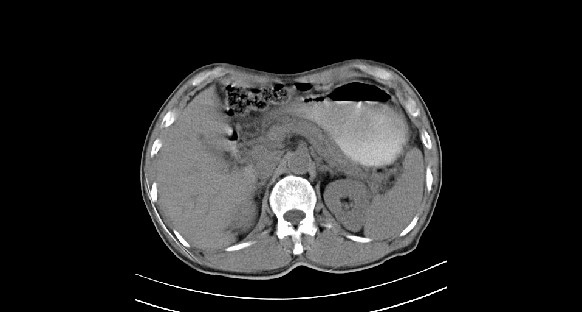

男性,70岁,体检b超发现左肾占位,请各位战友发表一下观点

左肾有两个病灶,且较大的病灶内可见点状钙化灶,增强扫描边缘也是呈渐进性强化,中央部分未见明显强化